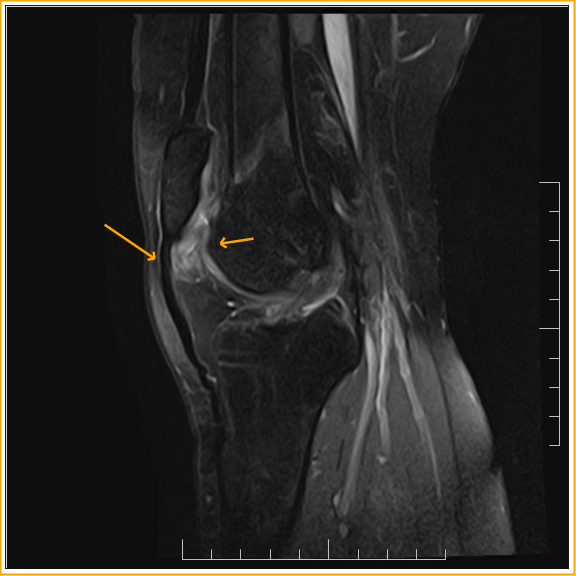

Синдром гоффа коленного 114 фото